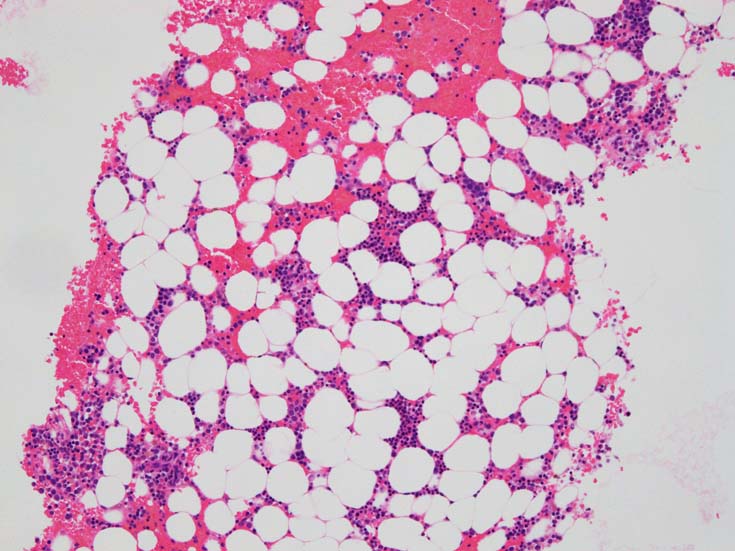

MDS症例のHbF発現.

サムネイル画像をクリックすると大きな画像が見られます.

MDSでの赤芽球HbF発現は, 陽性細胞はそれほど多くない印象ですが, この低形成性MDS症例では, 多くの陽性細胞がaggregatesを形成していました.